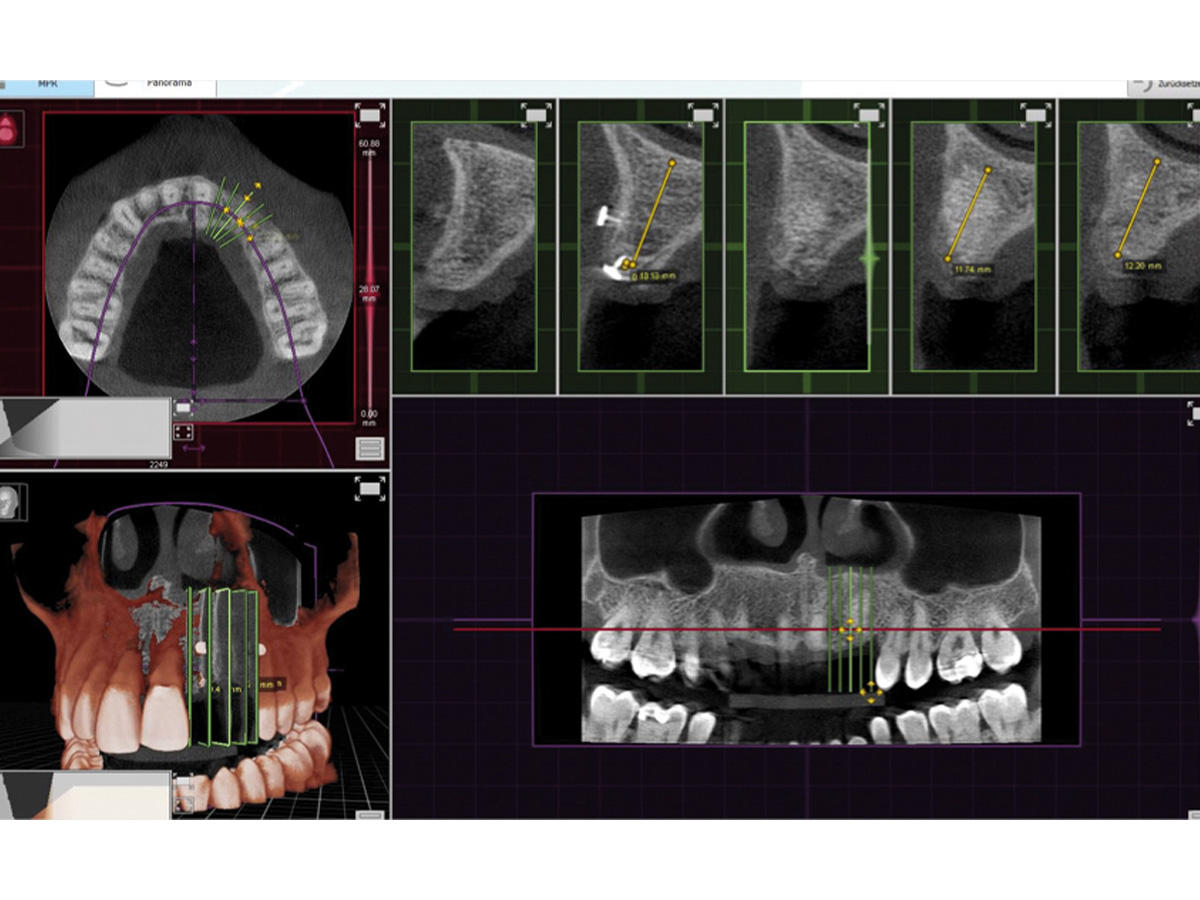

Abbildung 6

DVT präoperativ.